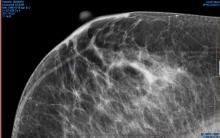

Hologic, Inc. announced that the Centers for Medicare and Medicaid Services (CMS) has released reimbursement rates for screening and diagnostic 3-D mammography. The action establishes national average payment rates for the Category I Current Procedural Terminology (CPT) code for 3-D screening mammography and creates a new add-on Healthcare Common Procedure Coding System (HCPCS) code for 3-D diagnostic mammography.

Fujifilm Medical Systems will highlight its women’s healthcare portfolio at the 2014 Radiological Society of North America (RSNA) in Chicago, Ill. The company will show enhancements to its Aspire Cristalle mammography system, released in July.